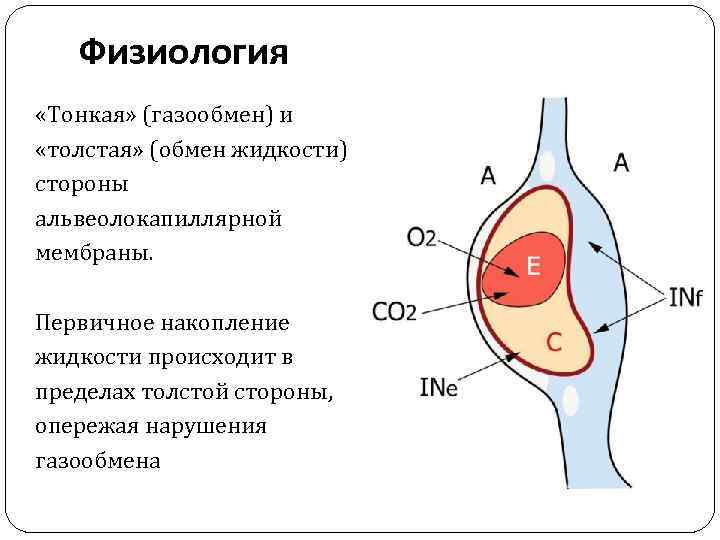

Физиология «Тонкая» (газообмен) и «толстая» (обмен жидкости) стороны альвеолокапиллярной мембраны. Первичное накопление жидкости происходит в пределах толстой стороны, опережая нарушения газообмена

Физиология «Тонкая» (газообмен) и «толстая» (обмен жидкости) стороны альвеолокапиллярной мембраны. Первичное накопление жидкости происходит в пределах толстой стороны, опережая нарушения газообмена